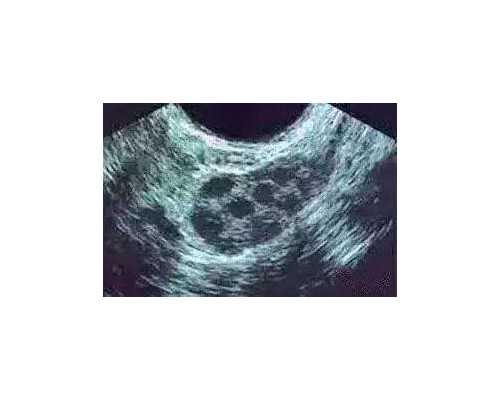

擅长实验室相关操作;胚胎室准备、操作、质量控制;体外受精、卵胞浆内单精子显微注射(包括 TEST 新鲜和冷冻 精子)操作;精子优化处理、辅助孵化(AH)技术、体外受精、胚胎和囊胚冷冻、复苏(FET)。